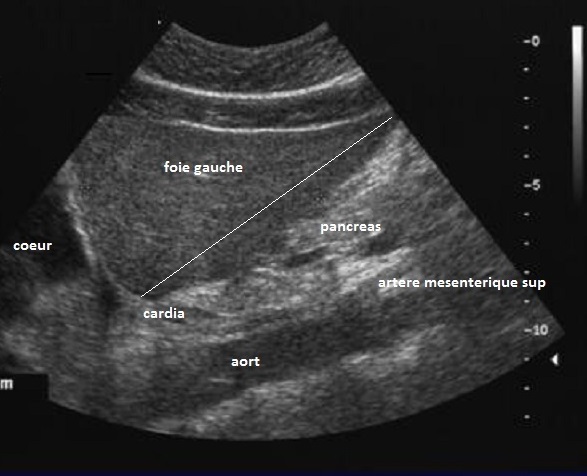

Image echographique du foie et des vaisseaux

normales ( echo-anatomie ) :

Ils y avaient plusieures plans

de coupe pour exploration echographique des voies biliaire . Entre eux

ils y avaient quelcoupe de base pour etudie la

vesicule biliaire et voie biliaire :

| |

- Coupe long sagitale de l;a ligne median

atravers foie gauche et aorte abdominal |

Le volume hepatique est verifie sur les coupes sagittales

passant la ligne mediane a travers l'aorte pour le foie

gauche et par la ligne medio-claviculaire droite pour le

foie droit. La mesure de distance entre le point le plus

haut du bord anterieure du foie avec la cardia de l'estoma

est la mesure echographique du foie gauche , normalemat

100mm . La distance de bord anterieuse du foie a la ligne

medioclaviculaire droit au point inférieur du foie, comme la

mesure echographique du foie droit , nosmalement 150mm . Les

contours hepatiques sont normalement parfaitement lisses, sa

capsules est fin liséré échogène . Le foie

est mobile à la respiration et a changements de posture. Il

y avait un interface entre le rein droit et le foie c'est

l'espace de MORISSON. Le parenchyme hépatique est

parfaitement homogène et finement granuleux. Sa tonalité

etre a peu près équivalentes à celle du cortex du rein droit

Sur la coupe long

sagital de la ligne median , on peut verifier volume

du foie , la distance du foie gauche normalement

100mm . |